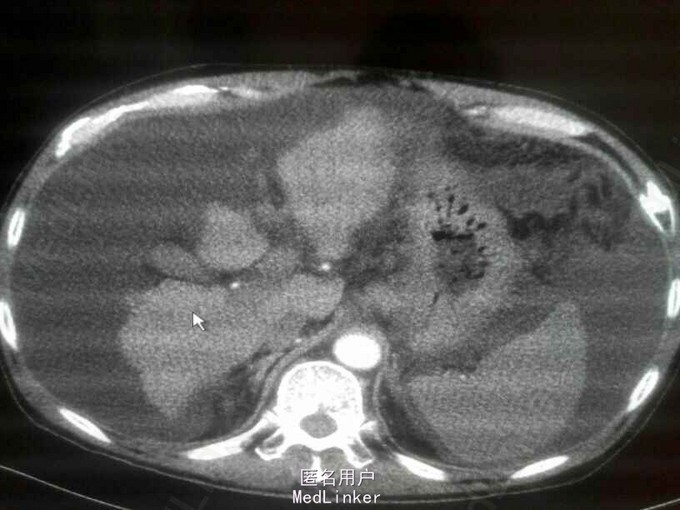

查体:全身皮肤黏膜黄染,颈前可见数玫蜘蛛痣,巩膜黄染;肝浊音界存在,移动性浊音阳性,腹部膨隆,软,下腹压痛,无反跳痛,未触及腹部包块,肝脾触诊不满意,肠鸣音减弱,双下肢凹陷性水肿。 辅助检查:腹部B超,1.肝硬化2.腹腔大量积液(深约13.8㎝)腹部CT:1肝方叶局限性膨隆2肝硬化,门静脉高压3胆囊炎8月29日 凝血:纤维蛋白原 0.80g/L,凝血酶原时间20.9秒,8月30日 降钙素原0.63ng/ml,生化:钾离子5.77mmol/L,谷草,51IU/L,白蛋白20.8g/L,直接胆红素:79.1umol/L,间接胆红素:82.5umol/L,总胆红素,161.6umol/L,肾功:血肌酐 171umol/L,9月2日 血培养提示大肠埃希菌,9月7日复查:直接胆红素:69.8umol/L,间接胆红素:56.2umol/L,总胆红素,126.0umol/L,9月13号:直接胆红素:97.5umol/L,间接胆红素:82.0umol/L,总胆红素,179.5umol/L,白蛋白,23.8g/L;9月18日 直接胆红素:152.4umol/L,间接胆红素:83.1umol/L,总胆红素,235.5umol/L,白蛋白,25.0g/L;

诊断:1肝硬化失代偿2自发性腹膜炎3慢性乙肝 治疗: 入院后给予,埃索美拉唑抑酸,门冬氨酸鸟氨酸,还原谷胱甘肽针保肝,思美泰退黄;8月29日报危急值,凝血功能异常,给予维生素K1静滴,改善凝血;行腹腔穿刺引流腹水,每日引流量约800ml,给予美罗培南抗感染,8月30日查血小板 44×109/L,患者血肌酐高 171umol/L,考虑慢性肾功能不全,减少液体入量,9月1日停还原性谷胱甘肽针剂;9月4日 尿量600ml,下肢水肿加重,给予利尿合剂泵入,9月9日腹腔穿刺置管术后11天,复查B超:腹水最大深度约9.8㎝;9月12日 抗生素应用14天,停用抗生素,拔出引流管;9月13日 给予人血白蛋白纠正低蛋白血症,胆红素上升,给予还原性谷胱甘肽针剂保肝治疗,9月19日再次行腹腔穿刺引流腹水,9月21日患者出现肝昏迷症状,给予瑞干、支链氨基酸、乳果糖对症治疗后好转,大便常规提示,霉菌感染;9月22日继续给予美罗培南抗感染,大蒜素肠溶片抗真菌治疗;9月23日,患者腹水较前减少,仍有移动性浊音阳性,下肢轻度凹陷性水肿,患者出院。